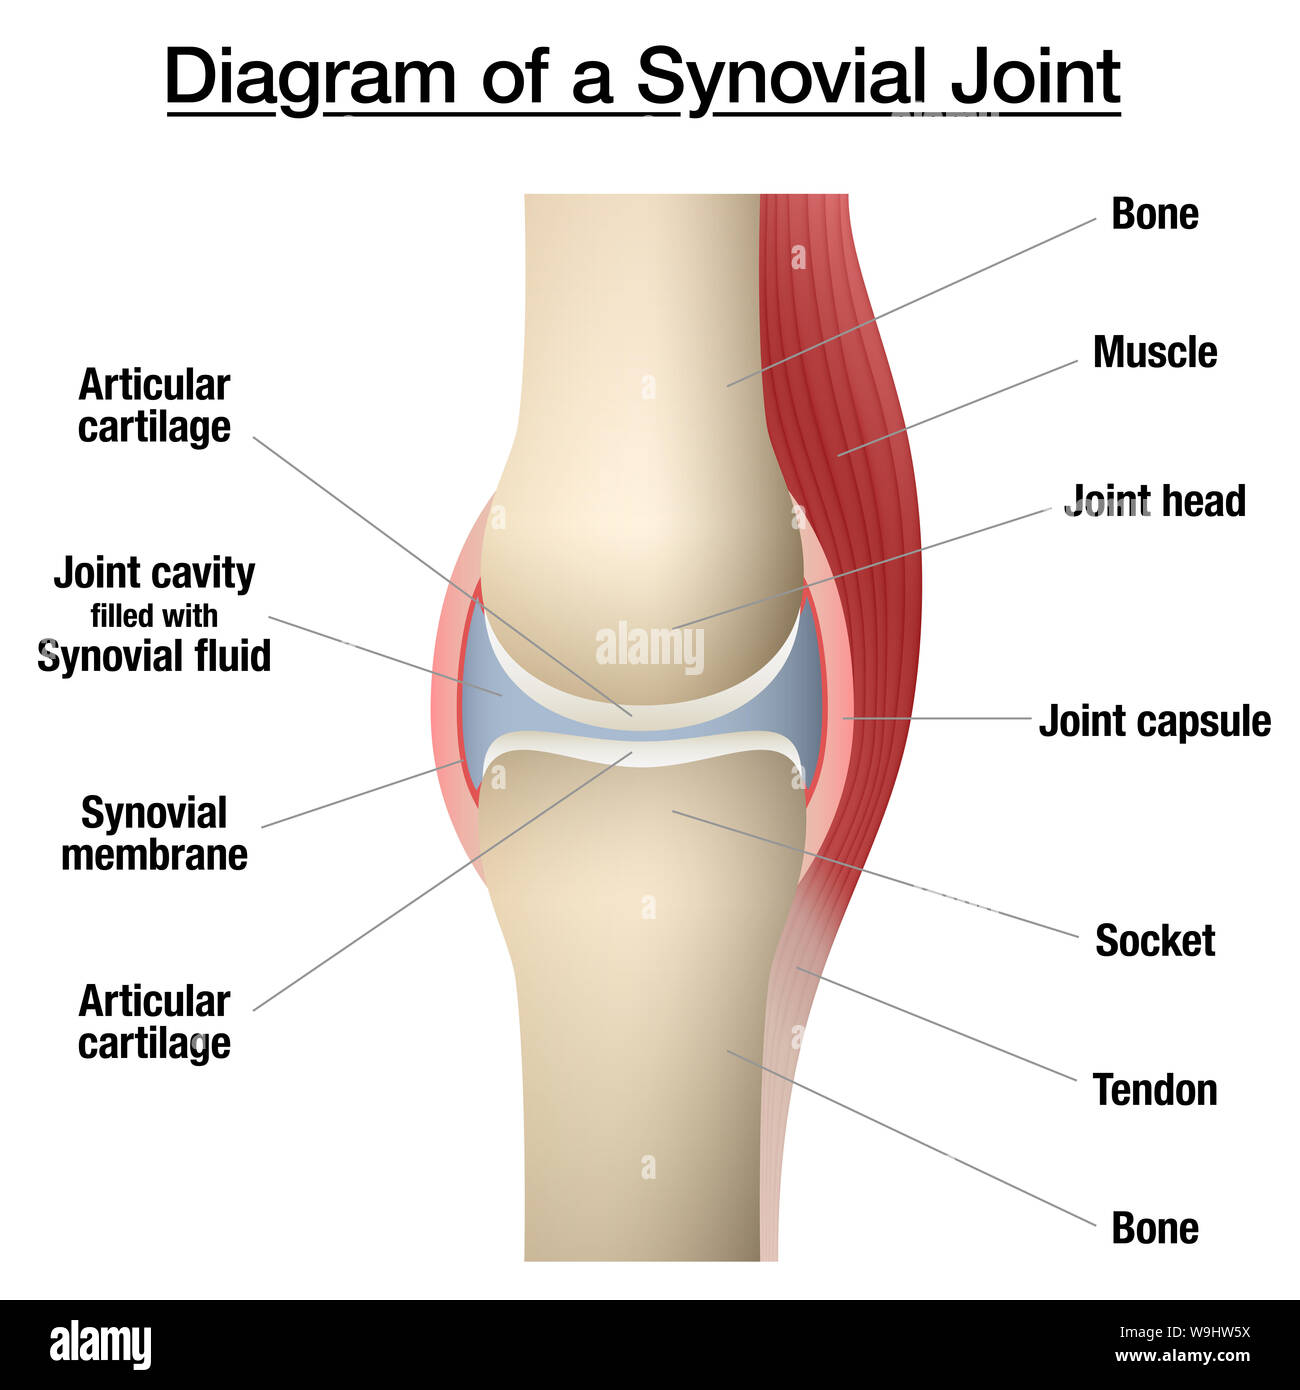

Synovial joint chart. Labeled anatomy infographic with two bones, articular cartilage, joint cavity, synovial fluid, muscle and tendon. Stock Photohttps://www.alamy.com/image-license-details/?v=1https://www.alamy.com/synovial-joint-chart-labeled-anatomy-infographic-with-two-bones-articular-cartilage-joint-cavity-synovial-fluid-muscle-and-tendon-image264080374.html

Synovial joint chart. Labeled anatomy infographic with two bones, articular cartilage, joint cavity, synovial fluid, muscle and tendon. Stock Photohttps://www.alamy.com/image-license-details/?v=1https://www.alamy.com/synovial-joint-chart-labeled-anatomy-infographic-with-two-bones-articular-cartilage-joint-cavity-synovial-fluid-muscle-and-tendon-image264080374.htmlRFW9HW5X–Synovial joint chart. Labeled anatomy infographic with two bones, articular cartilage, joint cavity, synovial fluid, muscle and tendon.